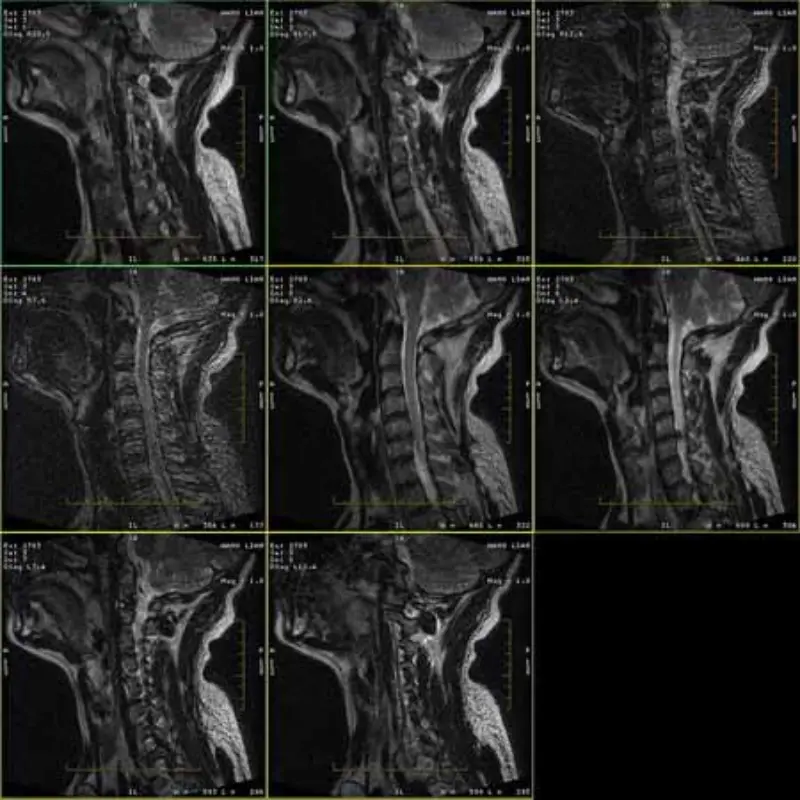

Зображення протоколів FRFSE та GRE мають привиди, а іноді зображення з низьким SNR з’являються в одній серії. Але зображення протоколу SE нормальні.

Подивіться, будь ласка, додайте зображення.